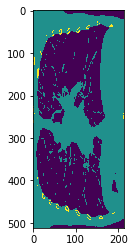

We have applied DeepDRR to anatomical landmark detection in pelvic X-ray: "X-ray-transform Invariant Anatomical Landmark Detection for Pelvic Trauma Surgery", also early-accepted at MICCAI'18: https://arxiv.org/abs/1803.08608 and now with quantitative evaluation in the IJCARS Special Issue on MICCAI'18: https://link.springer.com/article/10.1007/s11548-019-01975-5. The ConvNet for prediction was trained on DeepDRRs of 18 CT scans of the NIH Cancer Imaging Archive and then applied to ex vivo data acquired with a Siemens Cios Fusion C-arm machine equipped with a flat panel detector (Siemens Healthineers, Forchheim, Germany). Some representative results on the ex vivo data are shown below.